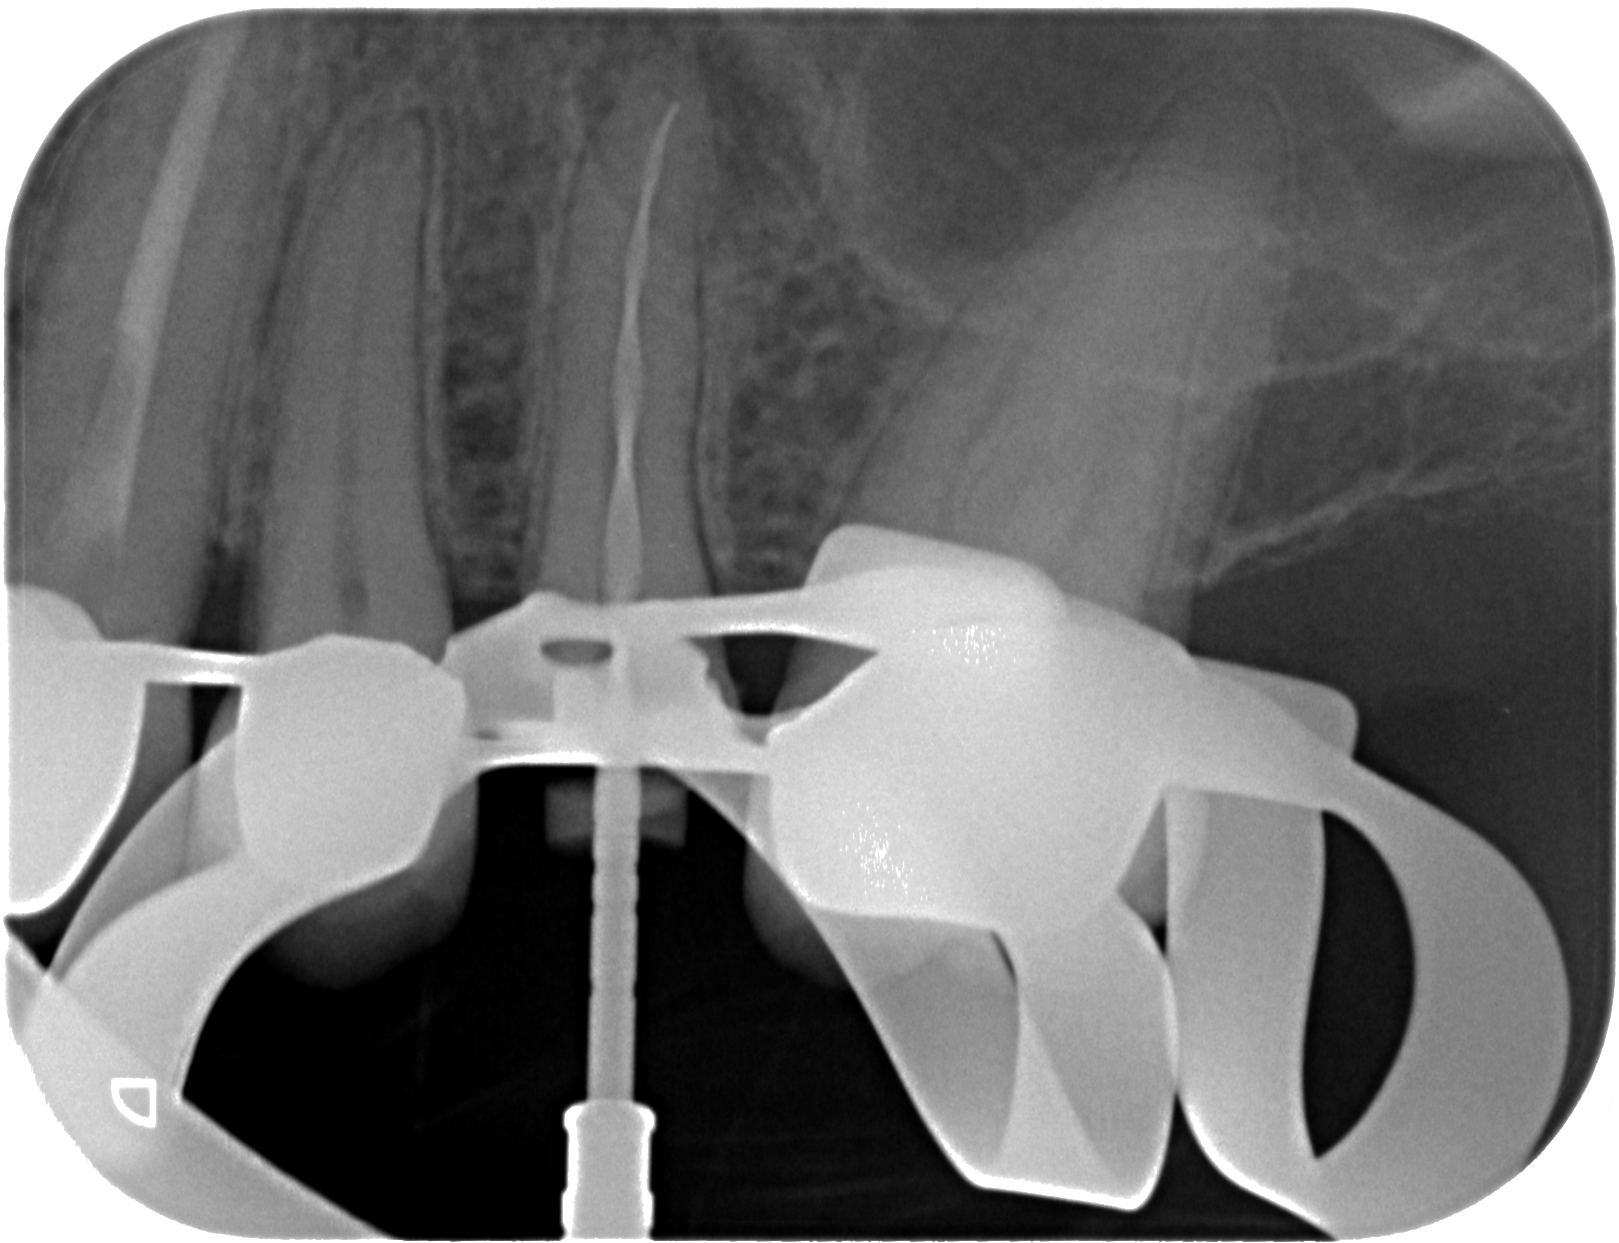

AA-11

1619 × 1243

Was braucht´s zur Heilung ?